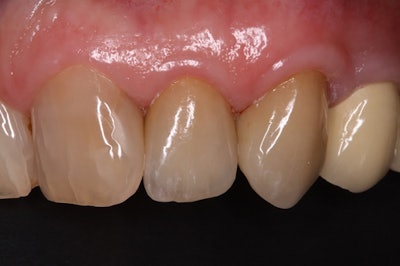

A patient's isogingivally fractured maxillary lateral incisor.Images courtesy of Graf et al. Licensed by CC BY 4.0.

The patient's smile at a 55.8-month follow-up visit.